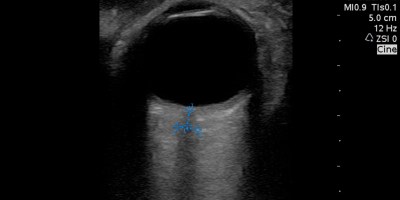

Sono Instruction, Sono Medical School, Sono Stuff Optic Nerve Sheath Diameter ONSD Review Useful in right setting #foamed #foamus #pocus #meded September 19, 2016 — 0 Comments

Sono Medical School, Sono Stuff National #Ultrasound Interest Group Journal Club – Topic ONSD #pocus #foamed #foamus August 2, 2016 — 0 Comments